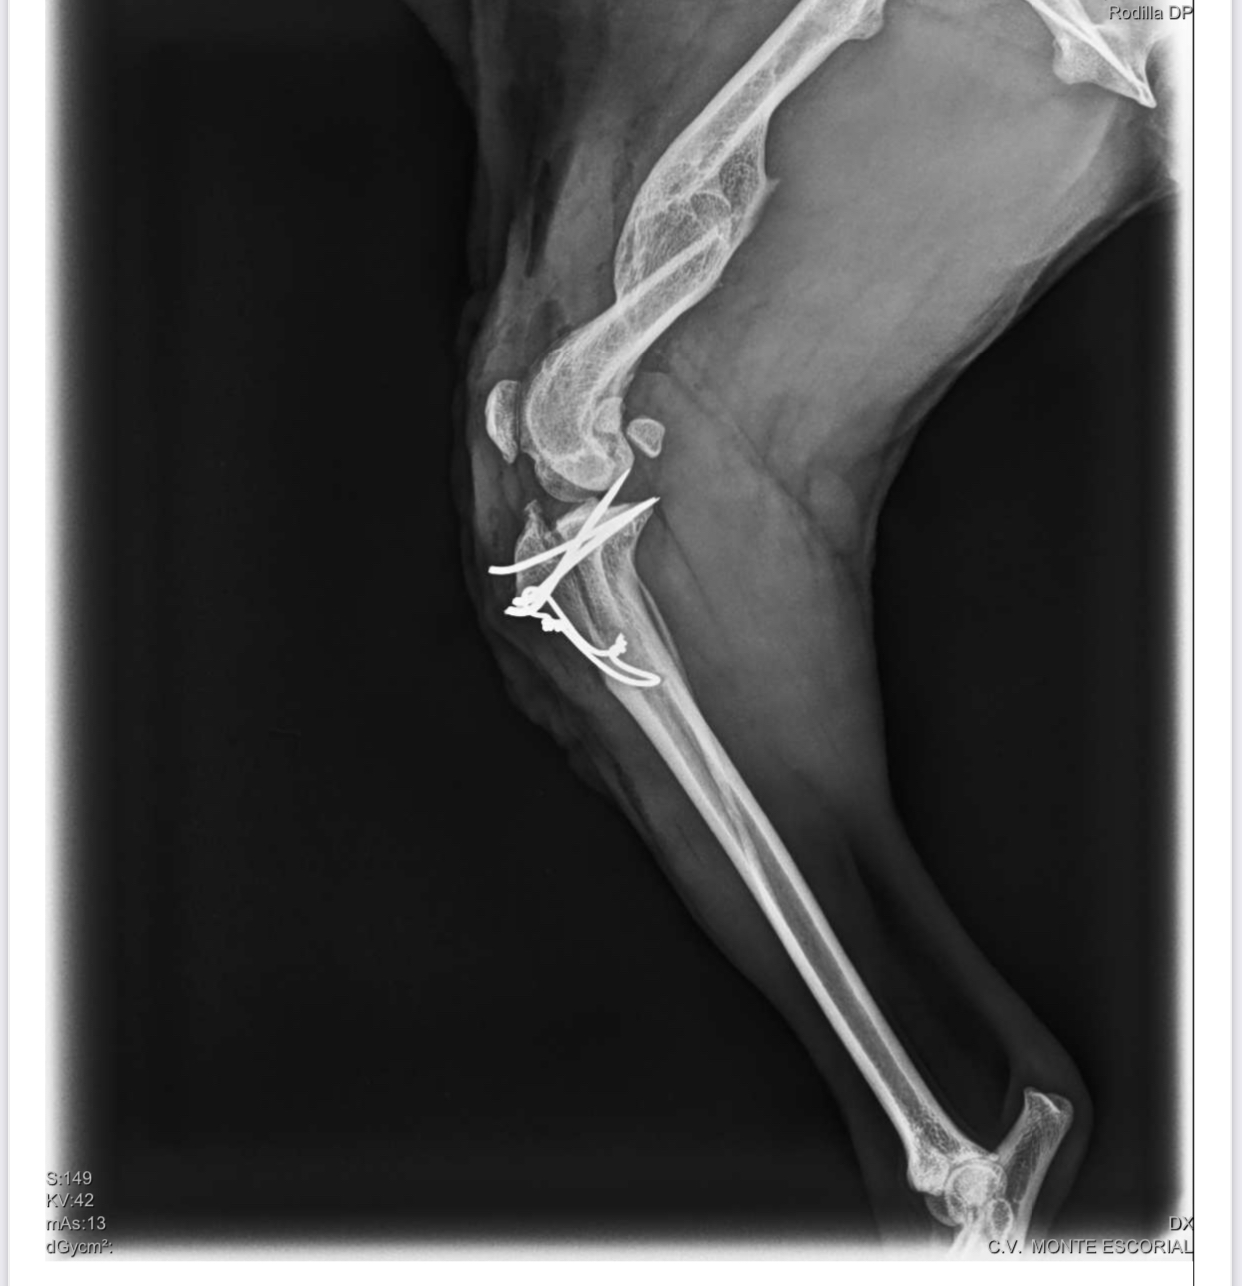

- SKADI: La podenca que llegó con fractura de pata; la han operado y ahora está en proceso de recuperación.